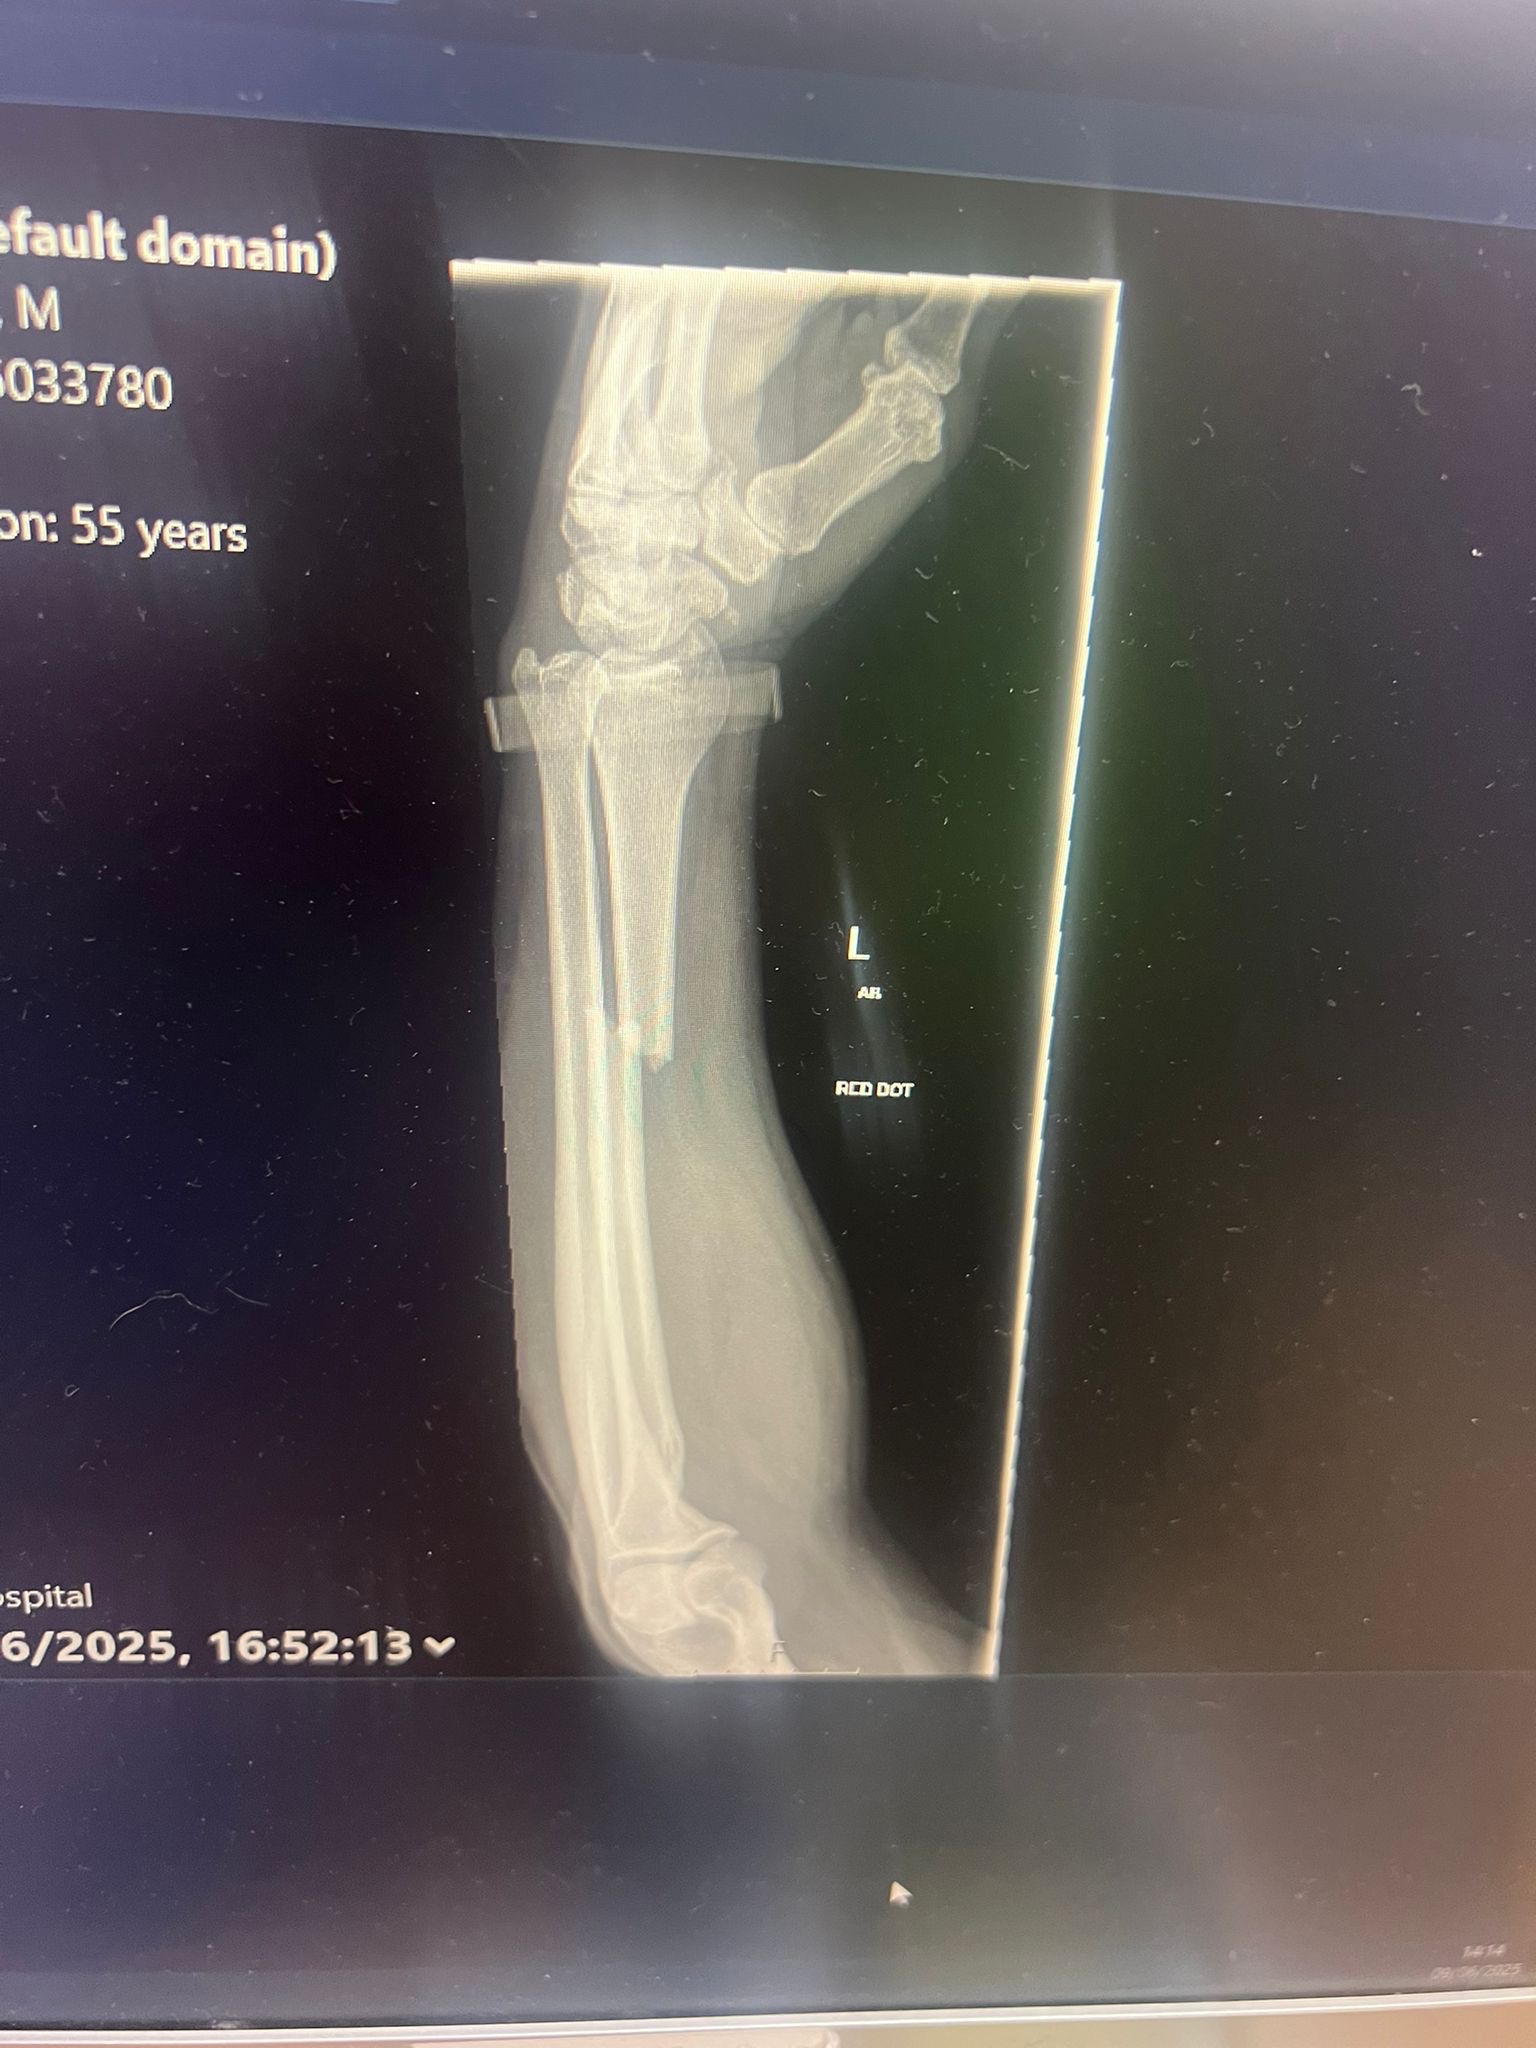

Mark suffered a displaced fracture of the radius bone in his left arm, requiring open reduction and internal fixation—in simpler terms, a small titanium upgrade. Unfortunately, this is beyond even the skills of our trusty Slick to fix this time.